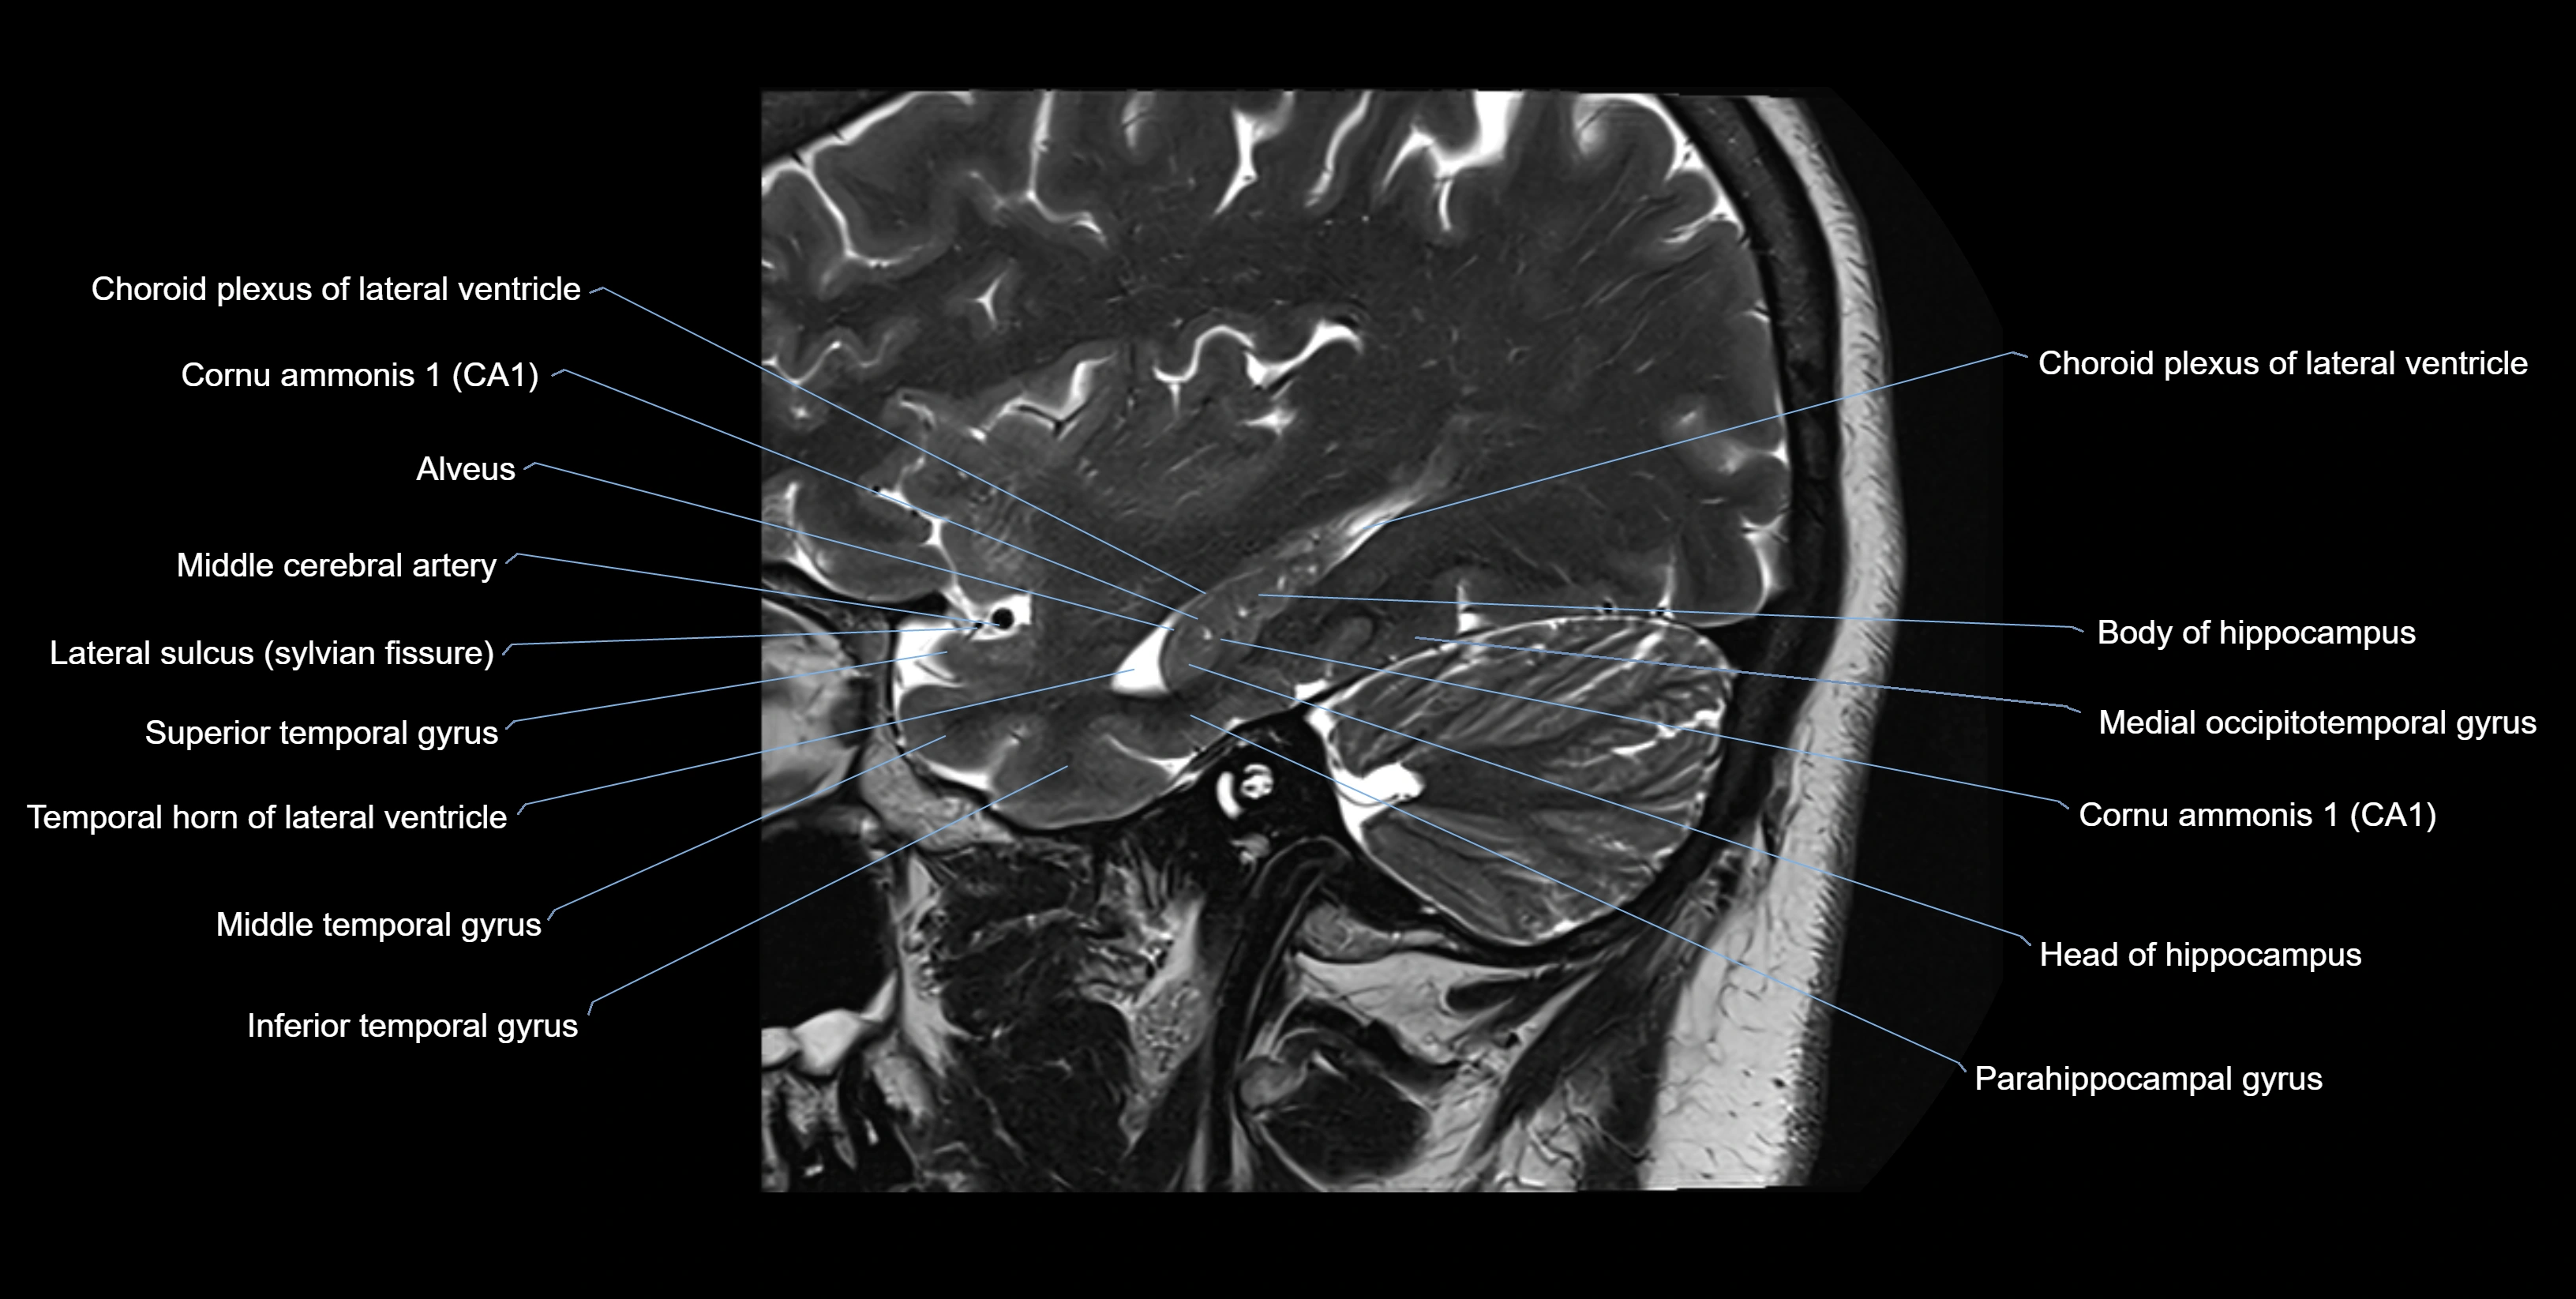

MRI images

image